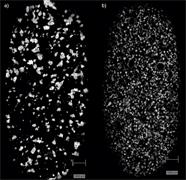

- Generate images of the formulations used in tablets, inhalers and nasal sprays at sub-micrometre spatial resolution

Rapidly generate images of your formulations with StreamLine™. This uses line focus illumination, allowing you to use higher laser powers without risk of sample damage, thereby reducing experiment times.

Ensure your chemical images are representative; use Renishaw's StreamLine. You can change resolution to suit your domain size and, because Renishaw's WiRE software can cope with massive data files, you can analyse over the entire sample surface. Powerful Renishaw features, such as Slalom (to ensure the whole surface is sampled) and HD imaging (to get crisp clear images), provide all the options you need, whatever your formulation.